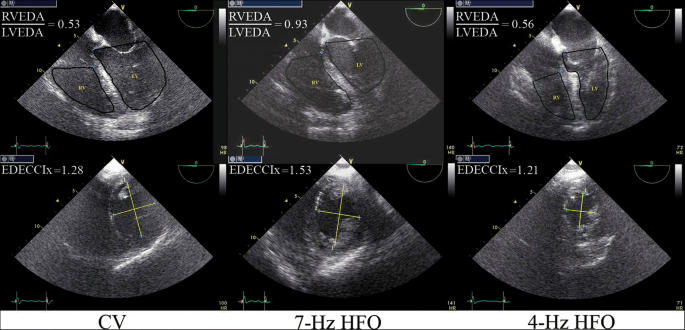

Examples of transesophageal echocardiographic (TEE) determination of two primary study outcome variables. Upper panel: determination of the right-to-left ventricular end-diastolic area ratio (RVEDA/LVEDA). Lower panel: determination of the end-diastolic eccentricity index (EDECCIx). The left vertical pair of images was obtained from study participant no. 12 during conventional ventilation (CV), the middle pair of images was obtained from participant no. 7 during 7-Hz high-frequency oscillation (HFO), and the right pair of images was obtained from participant no. 13 during 4-Hz HFO. In the lower panel (short-axis, transgastric views), “2” corresponds to the diameter of the left ventricle (LV) that was perpendicular to and bisecting the interventricular septum, whereas “1” corresponds to the diameter that was perpendicular to “2.” TEE measurements were repeated and averaged over 2–4 consecutive cardiac cycles (see also Additional file 1); EDECCIx was calculated as diameter “1”/diameter “2.” Description of figure modifications performed with Photoshop CC (Adobe Systems): upper panel, enhancement of the periphery of the right ventricle (RV) and LV using the “pen” tool and the “stroke path” command and enhancement of contrast of the middle image using the “adjust levels” command; lower panel, enhancement of diameter “1”/diameter “2” using the “line” tool. The original versions of the stored pairs of images are also provided in Additional file 1: Figure S1

Definitions

RV dysfunction: RVEDA/LVEDA > 0.6 to 0.9; RV failure: RVEDA/LVEDA > 0.9; Eccentricity index: quotient of 2 LV diameters plotted as shown in Fig. 2 (lower panel) [9, 22].